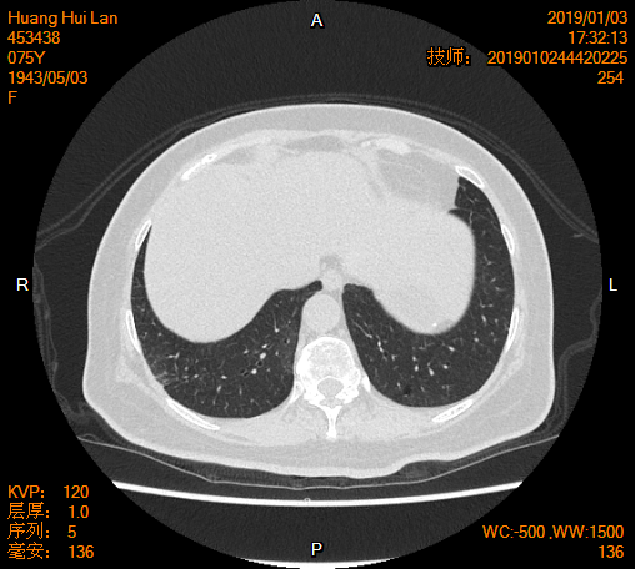

2016-04-13胸腹盆CT

2019-01-04胸腹盆CT